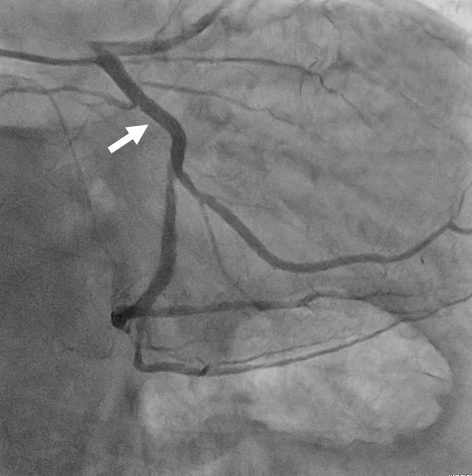

- junkankinaika-img01-20200229